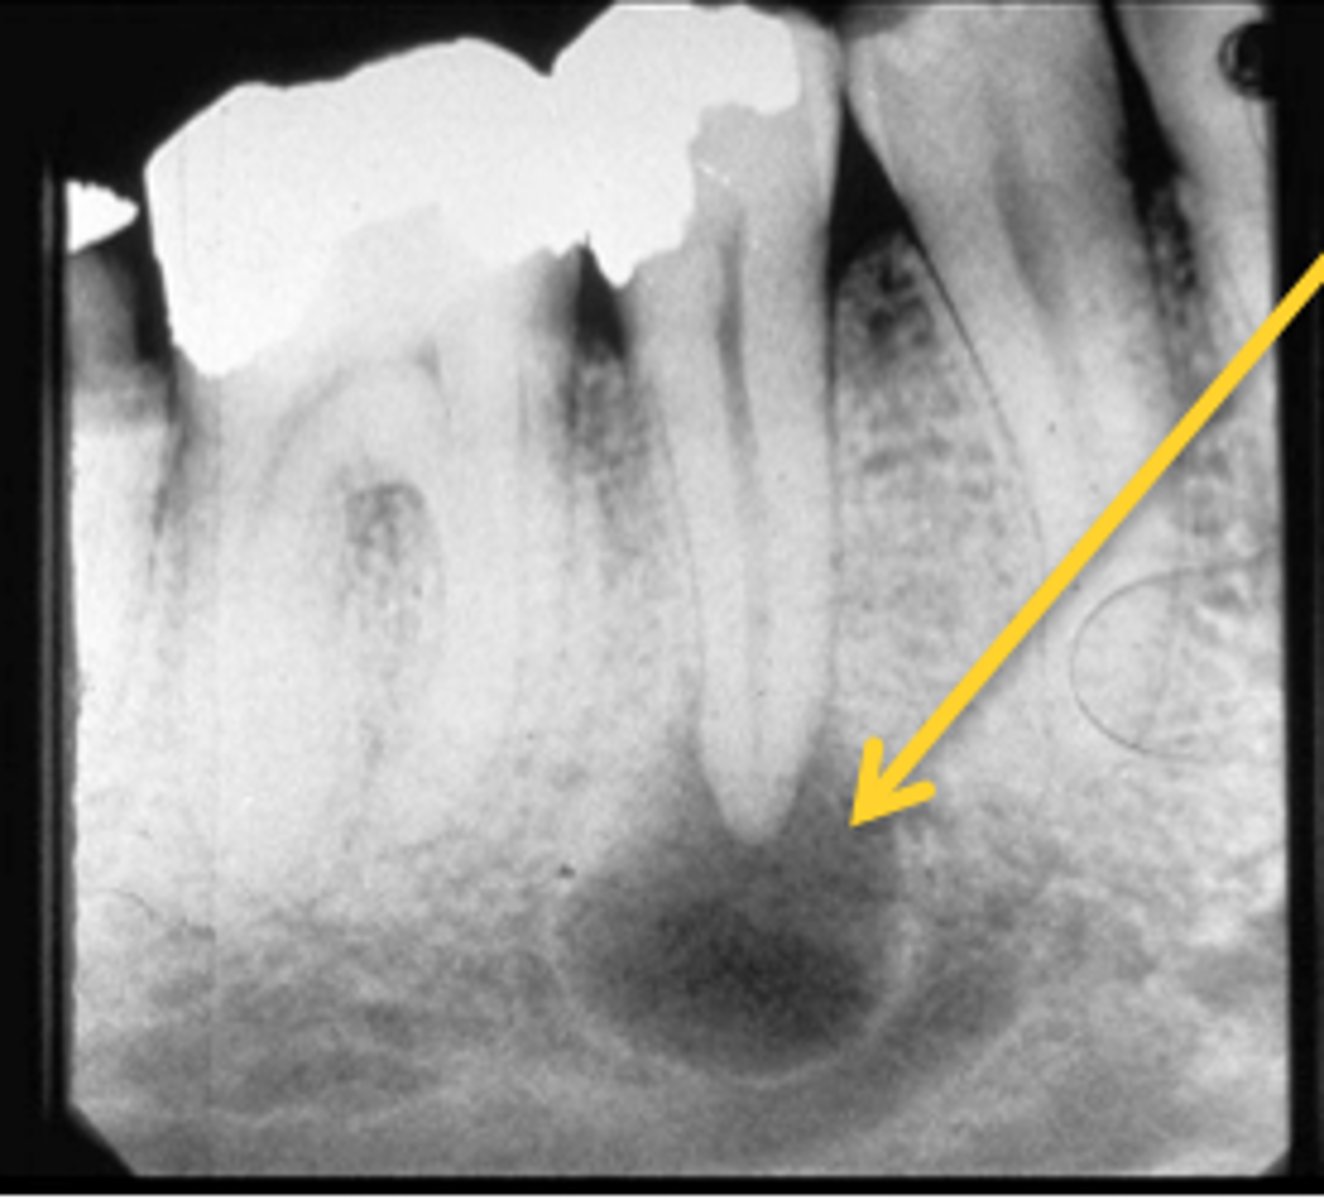

What is enostosis?

Dense bone island

What is the most common finding in radiographs?

Enostosis (one bone island)